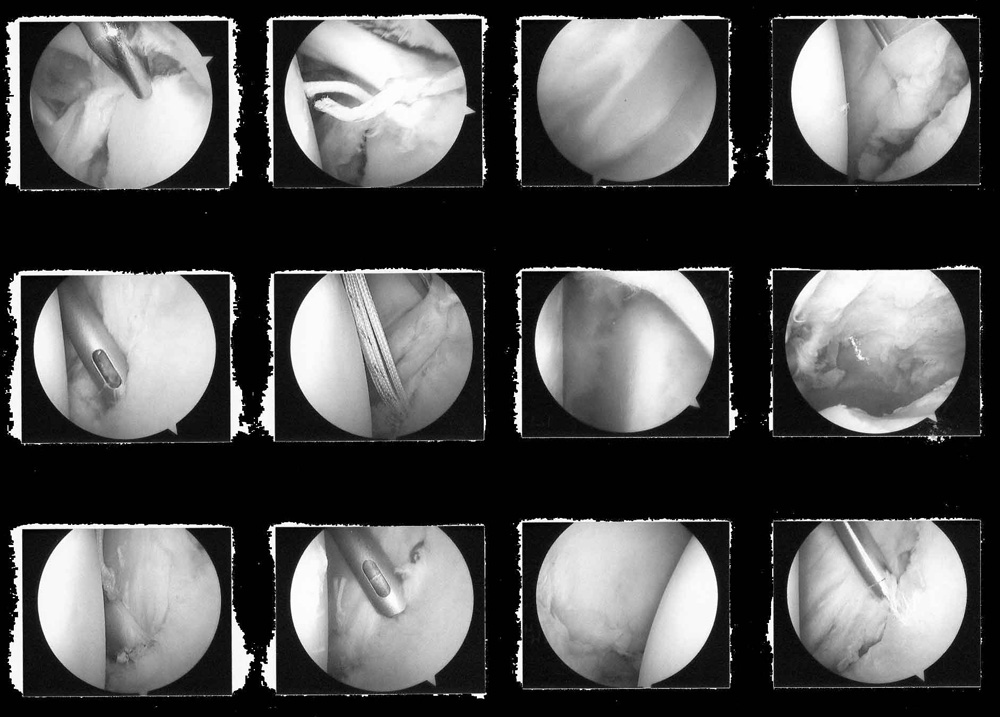

Arthroscopic Repair of Left Shoulder Joint Capsule and Tendons

4th October 2010

BANKART REPAIR